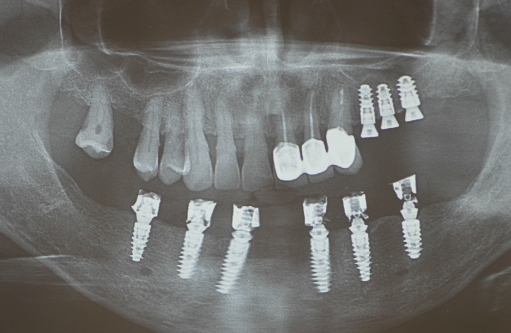

Pe baza scanărilor imagistice 3D (CBCT) se vor efectua măsurători ale înălțimii și lățimii osului mandibular, astfel încât medicul implantolog să poată decide dacă se pot insera implanturi direct sau este nevoie de adăugare de os în prealabil. Se realizează un ghid chirurgical care ajută la poziționarea precisă a implanturilor în os (Fig.3.6.4. dr. Ondine Lucaciu), iar în 24 de ore după această intervenție pacientul primește o punte provizorie fixă pe care o va purta un interval de 3-6 luni, perioadă necesară osteointegrării implanturilor, respectiv vindecării (Fig. 3.6.5). Această lucrare provizorie va fi înșurubată în 6 puncte, în cele 6 implanturi inserate în mandibulă (Fig. 3.6.6).

Lucrarea finală se va înșuruba pe componentele protetice ale implanturilor (Fig. 3.6.10 și 3.6.11), iar perforațiile de acces pentru șuruburi (Fig. 3.6.12) vor fi acoperite cu material compozit (Fig. 3.6.13). După fixarea definitivă (Fig. 3.6.14) puntea poate fi oricând detașată de către medicul dentist la nevoie, prin simpla îndepărtare a materialului compozit și desfiletarea șuruburilor de fixare.